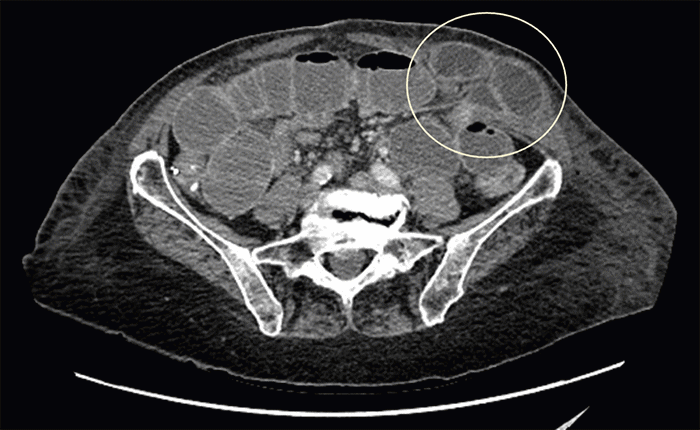

On postoperative day (POD) 2, after ambulating, the patient developed a firm, painful bulge at the LAAL 6 mm port site. She had not yet had a return of bowel function. Examination revealed a soft, non-distended abdomen with tenderness localized to this port-site bulge, which was initially suspected to be a hematoma. Abdominal X-rays obtained on POD 2 showed minimally dilated small bowel loops in the LUQ, no pneumoperitoneum, and diffuse subcutaneous emphysema throughout the left abdominal wall soft tissues (Figure 2). The lack of bowel function was attributed to resolving postoperative ileus, and she was continued on a full fluid diet. However, on POD 5, she began to vomit. A CT scan of the abdomen and pelvis with oral and intravenous contrast was performed, which demonstrated a high-grade SBO secondary to a port-site hernia at the LAAL 6 mm trocar site (Figure 3), with no evidence of bowel ischemia.

Figure 3. CT Demonstrating Port-Site Hernia and Small Bowel Obstruction. Published with Permission.

Axial contrast-enhanced CT scan of the abdomen and pelvis obtained on POD 5. This image clearly depicts a high-grade small bowel obstruction caused by a segment of jejunum herniating through the fascial defect at the site of the prior left anterior axillary line 6 mm port